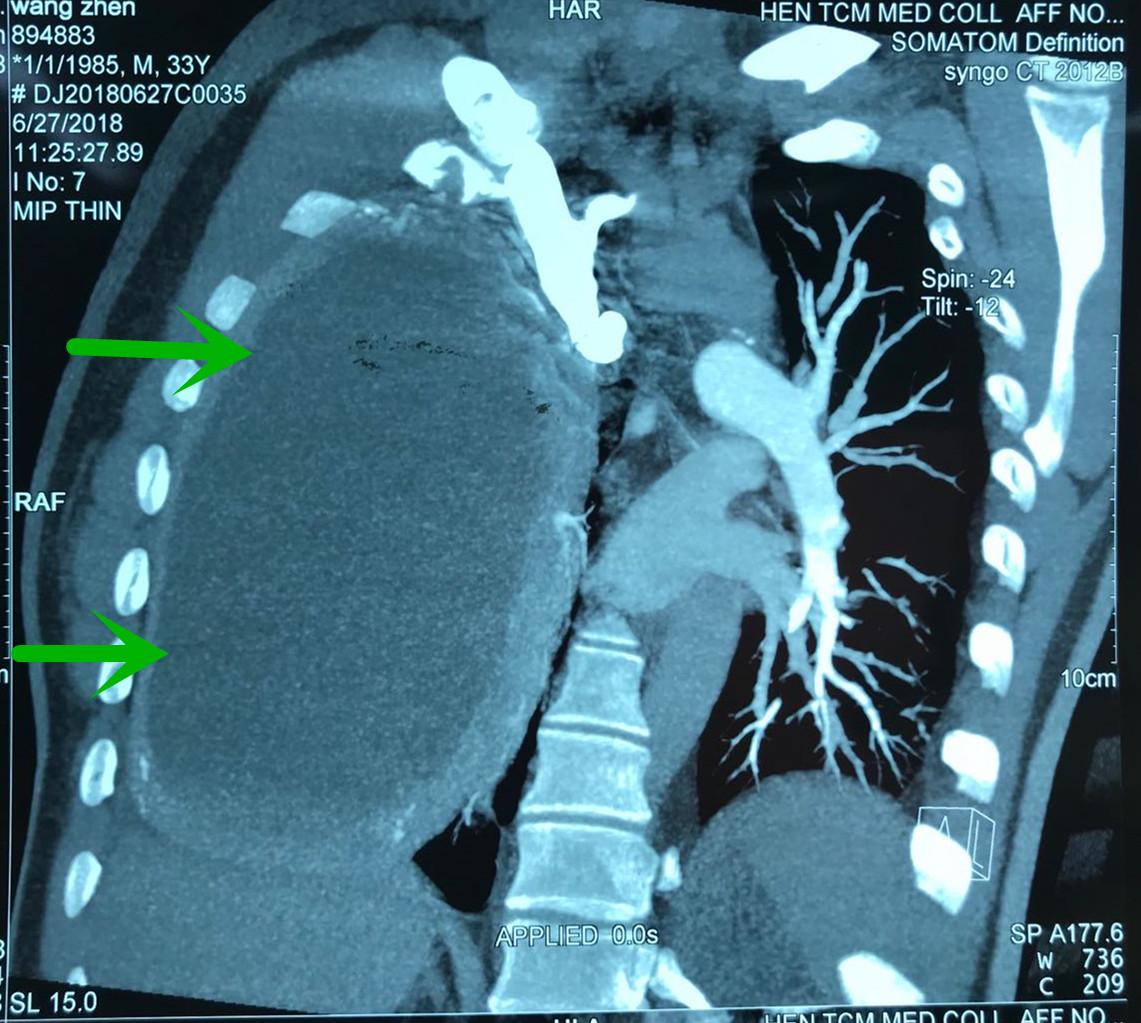

“拿到患者的检查结果,我们发现患者胸腔里长了一个足球大小的囊肿,已经快把右肺压瘪了,难怪他总是说胸闷、喘不过来气。”该院呼吸科王至婉教授说,患者胸腔内这个囊肿的体积有15×15×25cm那么大。由于囊肿的压迫,患者的右肺已经失去了呼吸功能,仅靠左肺来维持呼吸。

但这次李先生的情况不同寻常,由于右肺完全被挤压到肺门附近,加上右肺被压迫时间长,胸腔内囊肿巨大,可操作的空间极其狭小。同时囊肿和肺组织、主动脉、心包、膈肌、胸壁等周围重要组织粘连紧密,手术难度特别大,风险极高,手术中操作稍有不慎,就可能导致患者胸腔大血管破裂大出血,危及生命。